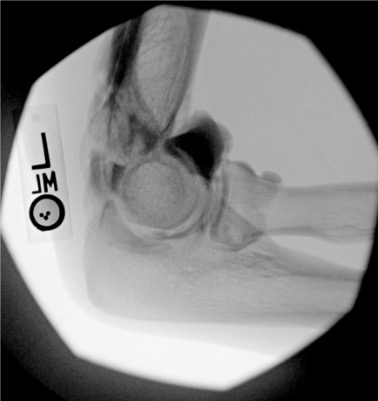

Elbow

Posterior (olecranon fossa)

Olecranon fossa with elbow flexed 90°; needle directed anteriorly into trochlear notch

8–10 mL

Intra-articular vs. extra-articular contrast distribution is the key fluoroscopic finding. Intra-articular: contrast flows freely along articular cartilage, fills joint recesses and capsular attachments. Extra-articular: contrast pools in soft tissue planes without joint recess filling — reposition needle before injecting diagnostic volume.